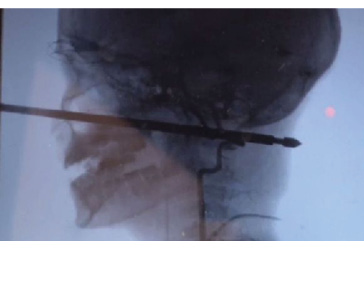

MAYBE he should have stuck to playing video games - an adventurous ten-year-old boy in the US state of Missouri is recovering after he was attacked by wasps in a tree house, falling to the ground where he was impaled face-first onto a meat skewer.

The metal (below) penetrated about 15cm into his skull, but miraculously missed his eyes, brain and major blood vessels.

The boy's horrified mother told the Kansas City Star that she saw her son walk into the house screaming with the skewer "just sticking out of his head".

Doctors say the youngster is likely to make a full recovery, although his voice may be slightly affected.